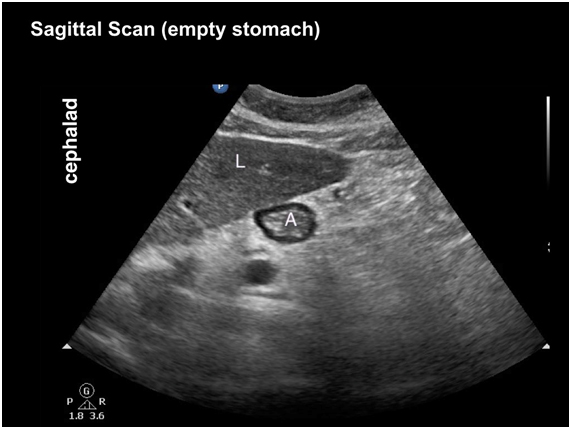

2) Ultrasound assessment by an operator (blinded) to qualitatively assessed in semi-recumbent and right lateral decubitus positions as ‘empty stomach’ or ‘contents present’.

Image from http://www.usra.ca/regional-anesthesia/specific-blocks/pocus/gastric.php